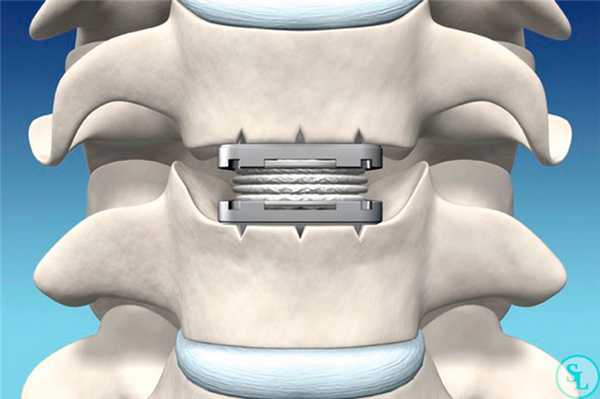

Эндопротез шейного межпозвоночного диска М6-С

Одним из самых современных и эргономичных имплантатов для шейного отдела позвоночника является эндопротез межпозвоночного диска. Он полностью повторяет анатомию и биомеханику природного диска, что позволяет рассматривать его в качестве полноценного органозамещающего устройства.

- Искусственным фиброзным кольцом, изготовленным из волокнистого высокомолекулярного полиэтилена. Оно отвечает за обеспечение естественной амплитуды движения межпозвонкового диска.

- Синтетическим пульпозным ядром, для производства которого используется вязкоэластичный полимер. Его свойства полностью соответствуют натуральному пульпозному ядру, что гарантирует правильное осевое сжатие.

- Опорными платформами с титановым напылением, расположенными по обеим горизонтально ориентированным сторонам эндопротеза. Они обладают высокой прочностью и стойкостью к механическим нагрузкам, что обеспечивает сохранность остальных компонентов конструкции при выполнении физической работы пациентом.

Надежность фиксации протеза достигается за счет специально созданных ребер на опорных платформах и их пористости. Благодаря этому процессы остеоинтеграции протекают с высокой скоростью, а конструкция быстро приживается.